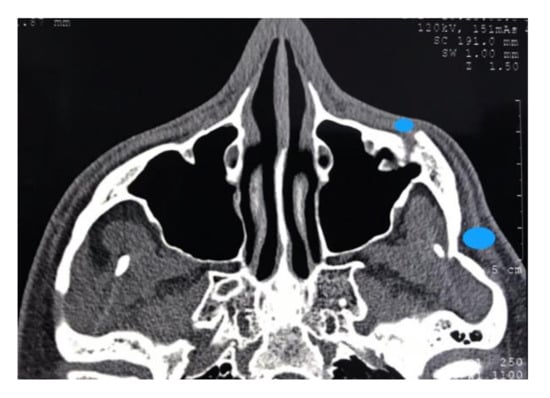

2.2. Case 2